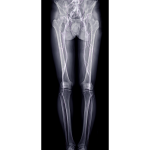

Los huesos que nos encontramos al dar una masaje en la espalda son: la columna vertebral, las escápulas (que ya las estudiamos con el miempro superior), las costillas y la parte superior de la pelvis (que también la estudiamos ya con el miembro inferior).

Costillas

Las costillas son huesos planos, curvos, que forman la mayor parte de la caja torácica. Son extremadamente livianos, pero altamente resistentes, lo cual contribuye a su tarea principal, que es la protección de los órganos torácicos internos.

Existen doce pares de costillas, las cuales articulan con la columna vertebral.

- 7 de ellas tienen una conexión directa con el esternón mediante su propio cartílago costal (se les llama costillas verdaderas).

- Desde la 8ª a la 10ª costilla son consideradas costillas falsas y se conectan con el esternón indirectamente mediante el cartílago de la costilla inmediatamente superior.

- Los dos últimos pares de costillas (11ª-12ª) y sus cartílagos terminan en el interior de la musculatura abdominal (costillas flotantes).